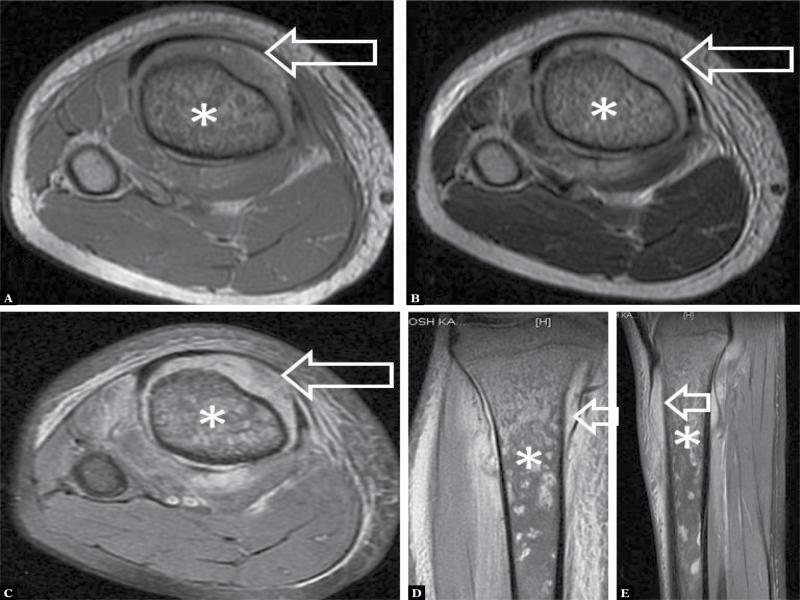

Fig. 4.

| Osteosarcoma | 1 | 5.56 |